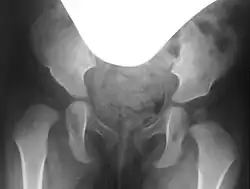

In hip dysplasia, the femoral head lacks sufficient lateral and anterior coverage, known as the acetabular rim. This inadequate coverage can cause the femoral head to slip upward and, depending on the severity, may lead to dislocation of the hip.[3]

Preoperative planning involves conventional pelvic X-rays, including pelvic overview and Rippstein view images, to assess joint misalignment, severity, and surgical planning. Rippstein views provide a lateral projection of the femoral necks.[7][8]